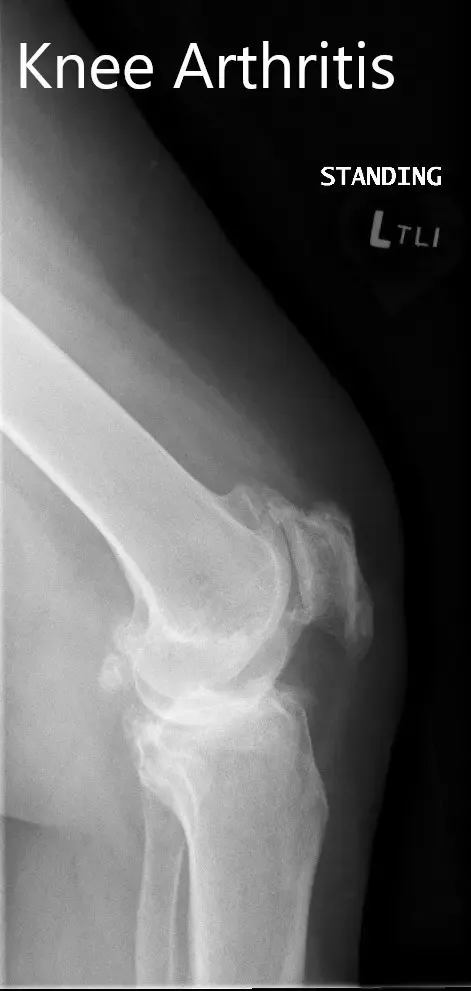

Imaging revealed severe tricompartmental osteoarthritis of the left knee with obliteration of the medial joint space and copious osteophyte.

Preoperative X-ray showing the lateral and the AP views